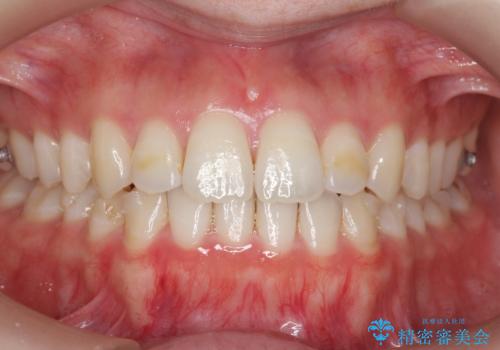

前歯のがたつきもしっかり治り、喜んでいただけました。

- インビザライン

- 1年